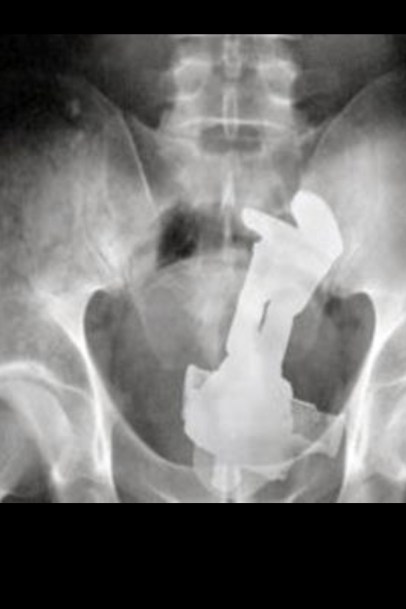

Today we’re going to take a look at how x-rays come into being, how we make them, and the physics behind how they let doctors see the object you “fell on.”

Almost immediately, the potential medical applications became apparent. Now, doctors could take a look into a patient without slicing them open, and medical problems were diagnosed easily and quickly. Modern CT scanners work in much the same way, but by taking x-ray photographs in “slices”, they can make a 3D of model a patient’s body by combining all of these slices together – just like how putting actual slices of a patient can model his body, but with much less screaming involved.

As we know, x-ray images show up because the rays travel through some materials better than they do others. Elements with higher atomic numbers do a better job of absorbing x-rays, while others allow them to pass through. For this reason, the calcium in bones blocks more radiation than the tissue surrounding it, creating an image that clearly shows the structure of the human body.